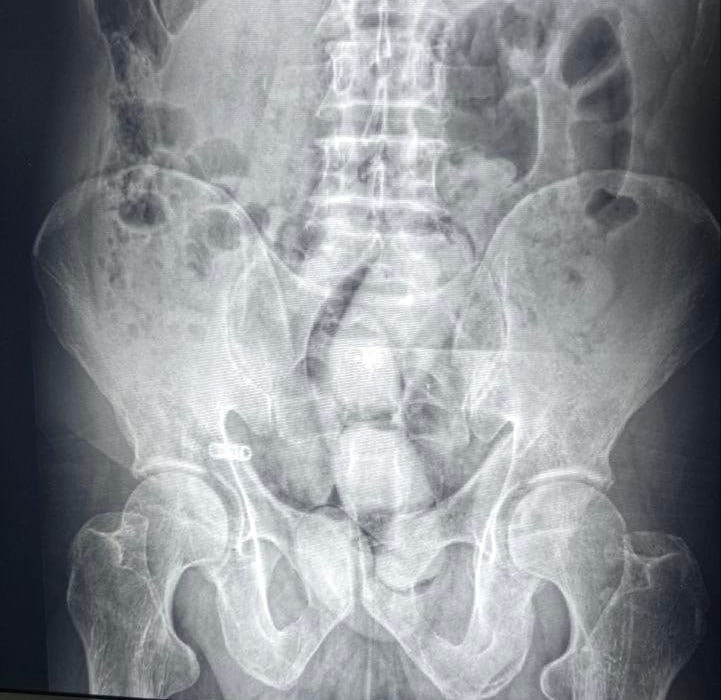

“Жартепа” чегара божхона пости орқали қўшни давлатдан кириб келган аёллардан бири божхона ходимининг эътиборини тортди. “Body scaner” қурилмаси орқали шахсий кўрикдан ўтказилганда унинг ички аъзосига 3 дона ўрам яширилганлиги аниқланди.

Мазкур пост орқали қўшни давлатдан кириб келган аёллардан бири божхона ходимининг эътиборини тортди. “Body scaner” қурилмаси орқали шахсий кўрикдан ўтказилганда унинг ички аъзосига 3 дона ўрам яширилганлиги аниқланди.

Ўрамлар шифокорлар кўмагида ва холислар иштирокида очиб кўрилганида уларнинг ичида жами оғирлиги 255 грамм опий гиёҳвандлик моддаси борлиги маълум бўлди.

Унга ҳамроҳлик қилаётган турмуш ўртоғи ҳам тезкор ходимлар томонидан дарҳол кузатувга олинди ва Самарқанд шаҳридаги шифохоналардан бирига олиб келинди.

Тиббий кўрик давомида ушбу шахснинг ички аъзоларидан 4 дона ўрамлар чиқариб олинди. Мазкур ўрамларга 541 грамм опий гиёҳвандлик моддаси жойланган экан.

Шундай қилиб, ушбу ҳолатда ўзидан "жонли контейнер" сифатида фойдаланган йўловчилар томонидан жами оғирлиги 796 гр. "опий" гиёҳвандлик моддасини олиб киришга уринишнинг олди олинди.